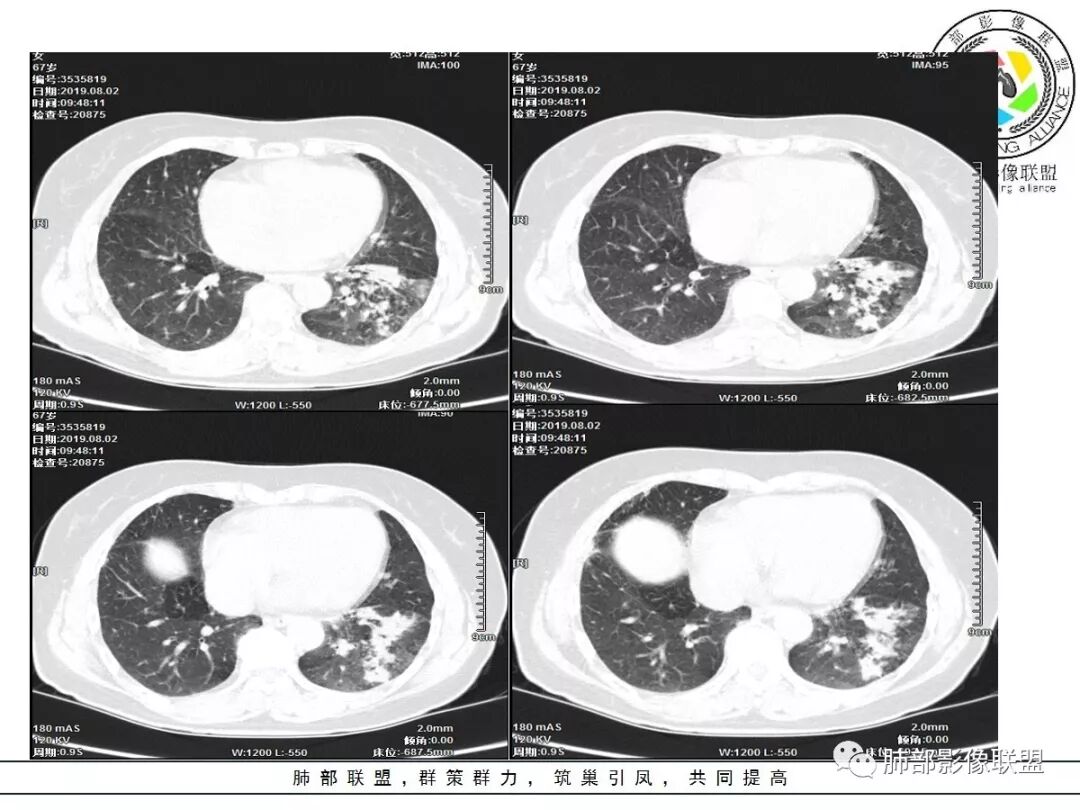

1、主病灶  左下叶斑片状、大片状致密影

2、两肺马赛克灌注

3、两侧肺门区钙化淋巴结

总共就这三大块

这三大块有没有联系?有没有相关性?

这三幅图是连续的,我们看到支气管中间这一幅狭窄了

大——小——大,狭窄后扩张

从这幅图看好像与周围病灶分界不清,支气管腔狭窄后扩张,支持炎性

2.左肺下叶片状影及多数有边界的结节影,较散,多形性,密度不均(注意许多老师提到这个特点还是比较明显的)。左肺下叶体积未见缩小。

3.病灶强化比较明显。

4.左下叶支气管壁增厚,管腔不均匀狭窄,没有堵塞